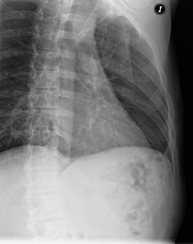

- Tòrax

- RX Tòrax

Tècnica que usa els raigs X a través de la qual s'obtenen imatges de la caixa toràcica (cor, pulmó, arcs costal, clavícules, etc.) per al seu estudi. - RX Ester

Tècnica que usa els raigs X a través de la qual s'obtenen imatges de les costelles per al seu estudi. - RX Columna dorsal

Tècnica que usa els raigs X a través de la qual s'obtenen imatges de la columna dorsal per al seu estudi. Indicacions: traumatisme, dolor, escoliosi. - Esofagograma